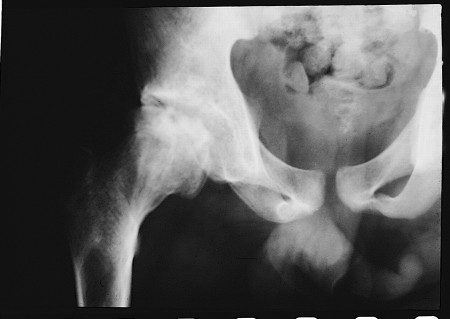

A apresentação de uma crise esquelética vaso-oclusiva depende da idade do paciente, pois acredita-se que os eventos se originem na medula óssea. Nas crianças, a medula óssea vermelha está presente em todos os ossos, incluindo os pequenos ossos da mão, o que é consistente com os achados clínicos de dactilite. Em crianças com mais de 8 anos de idade, a medula é mais comumente encontrada nas epífises e, em adultos, ela está limitada aos ossos esqueléticos axiais - por exemplo, a coluna vertebral, a pelve, o crânio e as porções mais proximais do fêmur e do úmero. Isso se ajusta clinicamente à incidência observada de infartos em ossos longos que aumentam com a idade, principalmente na cabeça do fêmur e do úmero.[Figure caption and citation for the preceding image starts]: Necrose avascular da cabeça femoral de paciente com anemia falciforme (hemoglobina SC) heterozigóticaExtraído de: Davies SC, Oni L. BMJ. 1997 Sep 13;315(7109):656-60 [Citation ends].

Nas crianças, a medula óssea vermelha está presente em todos os ossos, incluindo os pequenos ossos da mão, o que é consistente com os achados clínicos de dactilite. Em crianças com mais de 8 anos de idade, a medula vermelha é mais comumente encontrada nas epífises e, em adultos, ela está limitada aos ossos esqueléticos axiais - por exemplo, a coluna vertebral, a pelve, o crânio e as porções mais proximais do fêmur e do úmero. Isso se ajusta clinicamente à incidência observada de infartos em ossos longos que aumentam com a idade, principalmente na cabeça do fêmur e do úmero.[Figure caption and citation for the preceding image starts]: Necrose avascular da cabeça femoral de paciente com anemia falciforme (hemoglobina SC) heterozigóticaExtraído de: Davies SC, Oni L. BMJ. 1997 Sep 13;315(7109):656-60 [Citation ends].